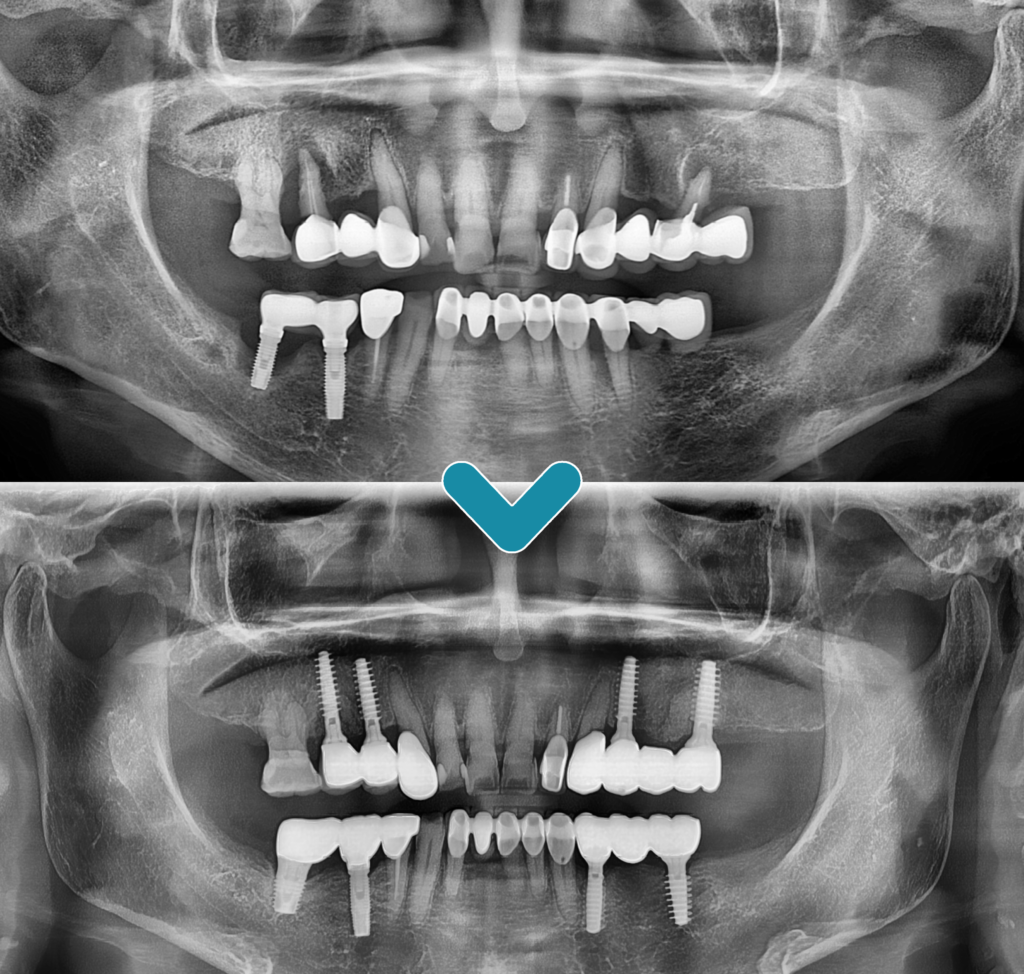

전체적인 파노라마 사진을

촬영해 보았을 때,

왼쪽은 이미 어금니 부위를 상실하여

브릿지 형태로 치료를 받아

힘을 받고 있는 치아들의

상태가 좋지 않음을 알 수 있었고

오른쪽은 기존 아래 임플란트 주위와

위쪽 자연 치아의 주위로 잇몸뼈가

많이 녹아 예후가 좋지 않음이 관찰되었습니다.

하여, 예후가 좋지 않은 치아들은

모두 발치한 후 임플란트 식립 계획을

수립하였습니다.

환.자분의 구강 상태를 충분히

고려하여 완산구임플란트 잘하는 프라임에서는

매직코어 최소침습 임플란트

수술의 장점을 설명드린 후

진행하였는데요.

잇몸뼈가 많이 녹아있는 상태로

좋지 않은 여건임에도 불구하고

절개의 과정 없이 안정적으로

임플란트 식립을 마무리할 수 있었고

식립해야 할 임플란트의

개수가 많아 걱정을 많이 하셨던

환.자분께서도 빠르고 편안한

치료 과정과 회복 속도에

만.족도가 높으셨습니다.